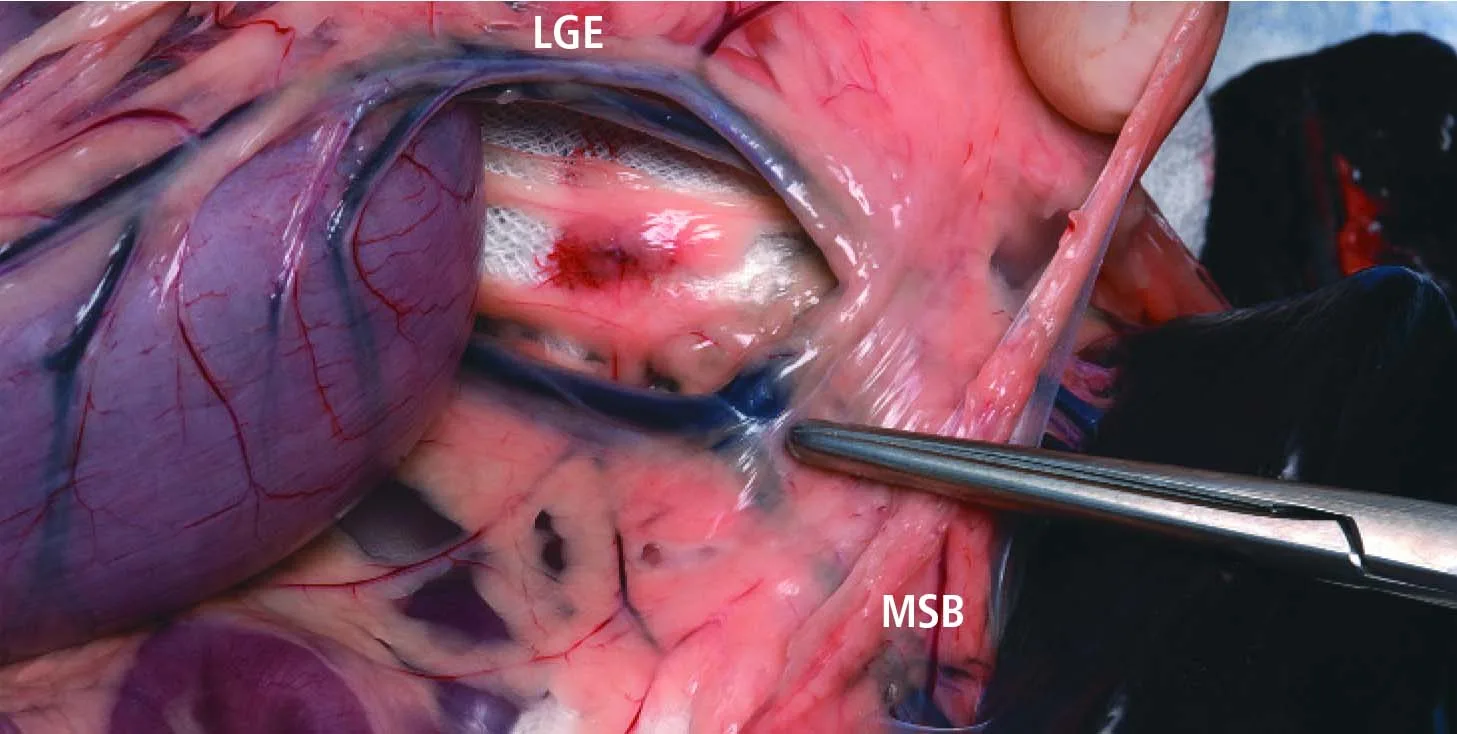

When the splenic hilus is not involved in the disease process and the stomach vasculature is to be preserved, break open the gastrosplenic ligament in an avascular area. Find the junction of the splenic artery and left gastroepiploic vessel; stay distal to this area during isolation of the final 3 pedicles listed below. In this figure, the splenic pedicle is viewed through a rent created in the omentum. The forceps point to the juncture of the main splenic artery, the main splenic branch (MSB), and the left gastroepiploic artery (LGE) coursing along the greater curvature of the stomach.